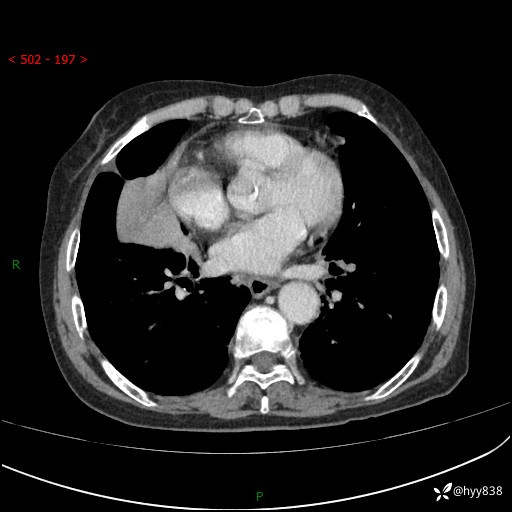

胸部CT增强(外院平扫)